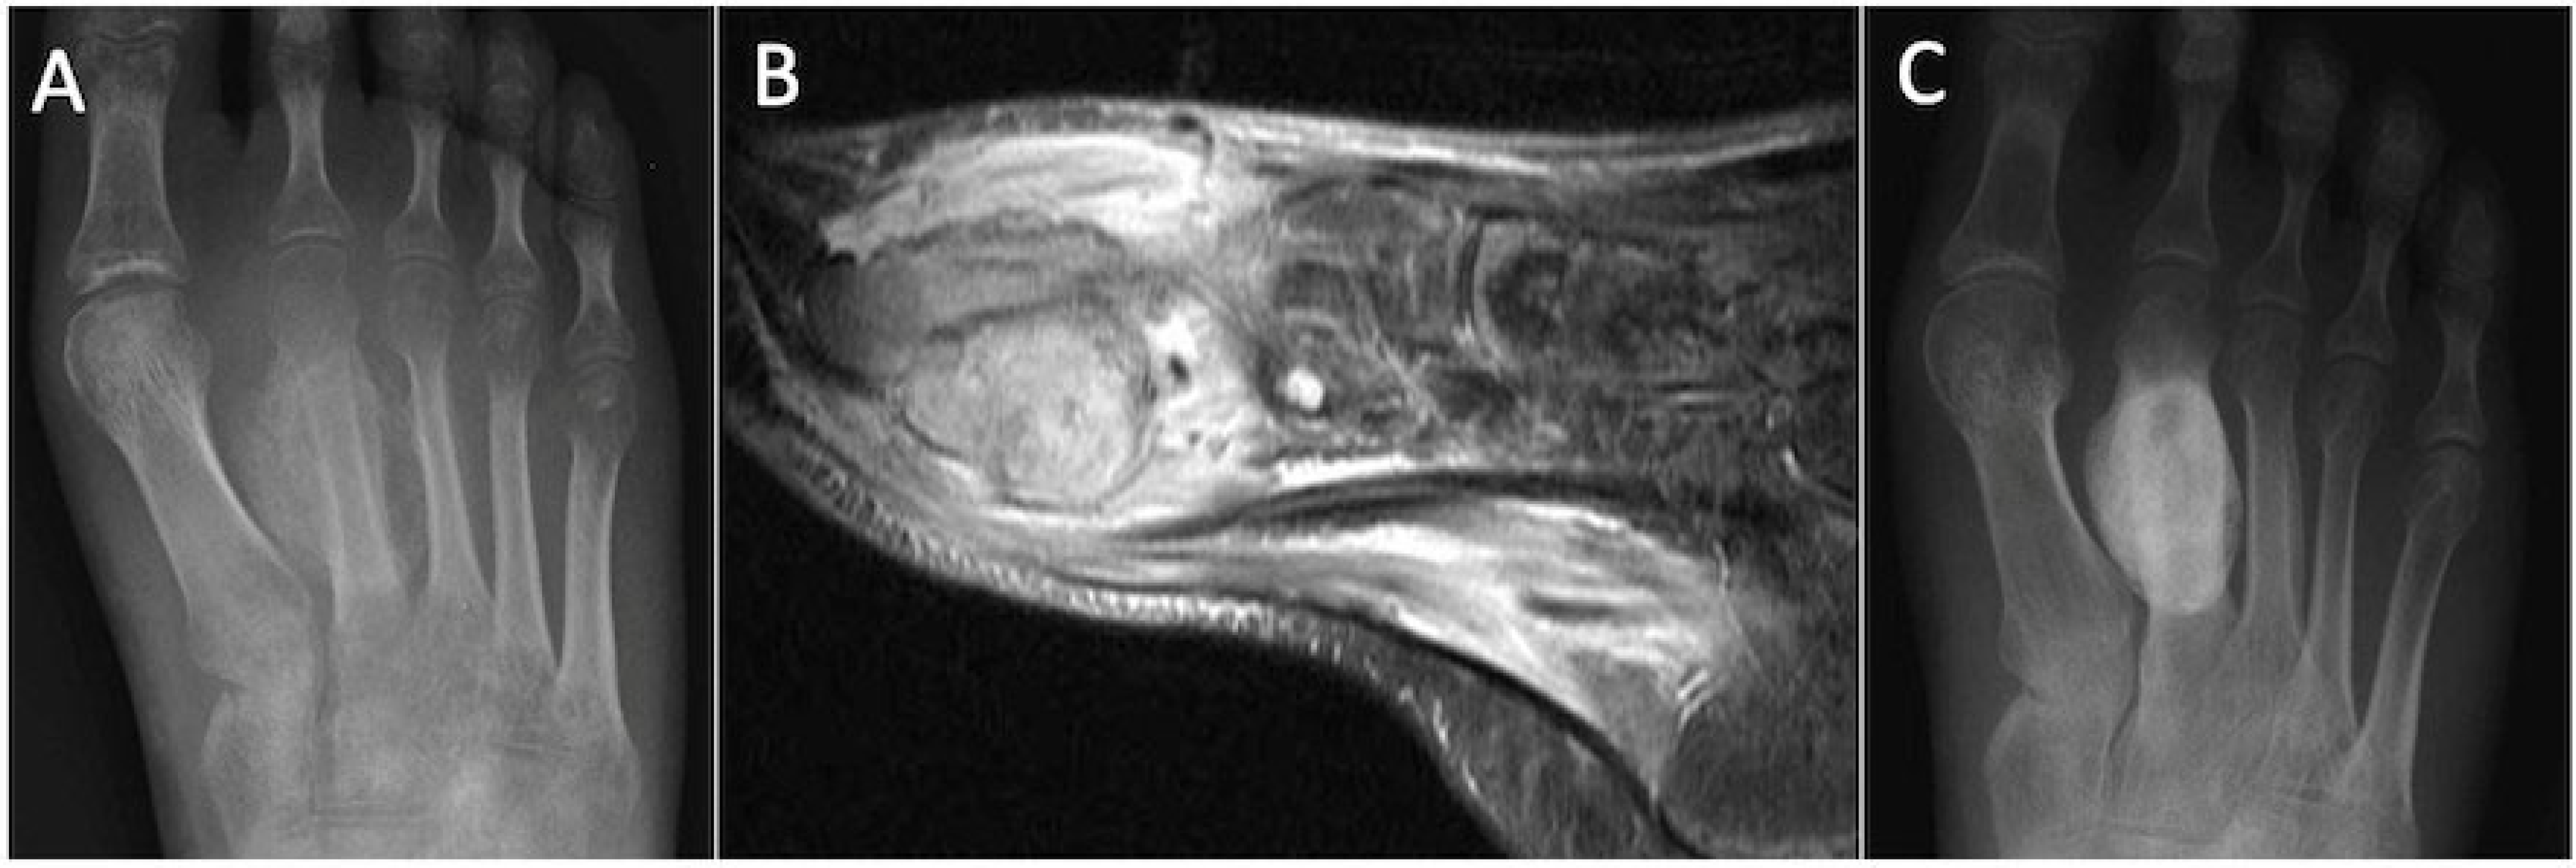

5.9. Subtendinous Bone Oedema

5.10. Gout